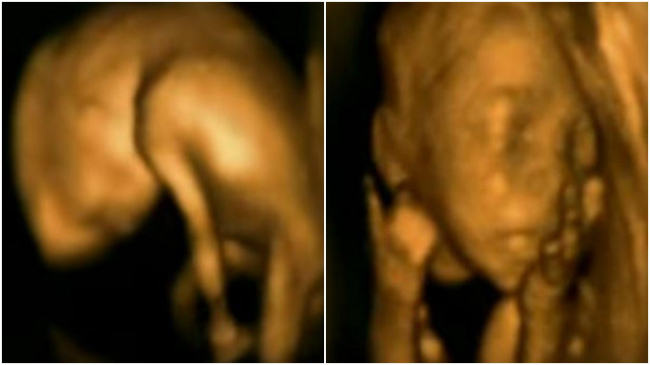

Ne întrebăm ce poate face micuțul în burtica mamei? Să mănânce – da, da, să mănânce prin intermediul cordonului ombilical și să bea lichid amniotic – precum și să doarmă liniștit cam 90% din timp. Însă, se pare, micuții își încep poznele încă din viața intrauterină. Probabil că fiecare mamă își amintește cu dragoste despre meciurile de fotbal sau discotecile organizate de micuț în burtă, arătându-i unde se află ficatul și rinichii. Acum puteți vedea această activitate frenetică, cum se spune, chiar din interior.